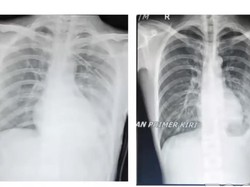

Lebih dari 120 ribu warga Indonesia meninggal dalam setahun akibat penyakit pernapasan yang berkaitan dengan polusi udara. Ini sorotan PDPI.